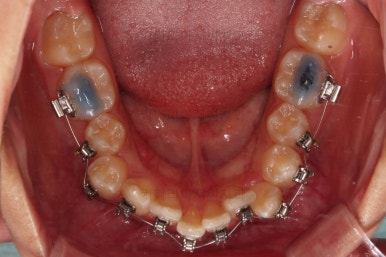

치료 종료시의 모습이에요.

총 21개월 걸렸고요.

발치를 중간에 결정했기 때문에 조금 지체된 면이 없지 않았으나 기간부터 치료 결과까지 만족스러운 치료였습니다.

치여링 가지런해졌고, 교합과 중앙선 등 입안의 모습이 매우 좋아졌어요.

불규칙하게 마모되어 있던 치아의 개별 형태도 약간씩 다듬어 드렸고요.

입매도 본인이 원하는 정도로 만들었고, 웃는 모습, 뻐드러졌던 각도도 매우 잘 개선이 되었네요.

기울어보이던 치열의 경사도 개선이 되었고요.

전반적으로 만족스러운 치료였습니다.